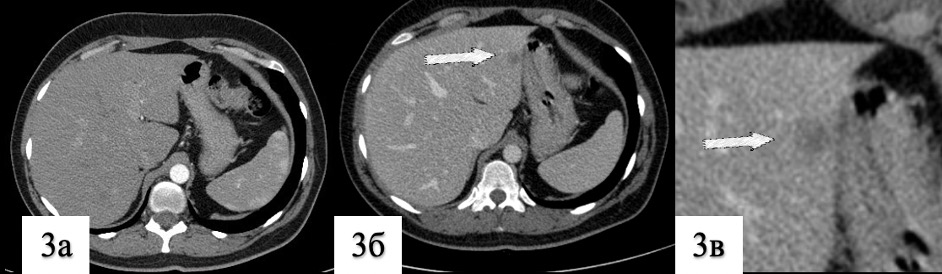

3. Рис. 3. КТ сканы живота | |

| Тема | ||

| Тип | Результаты исследования | |